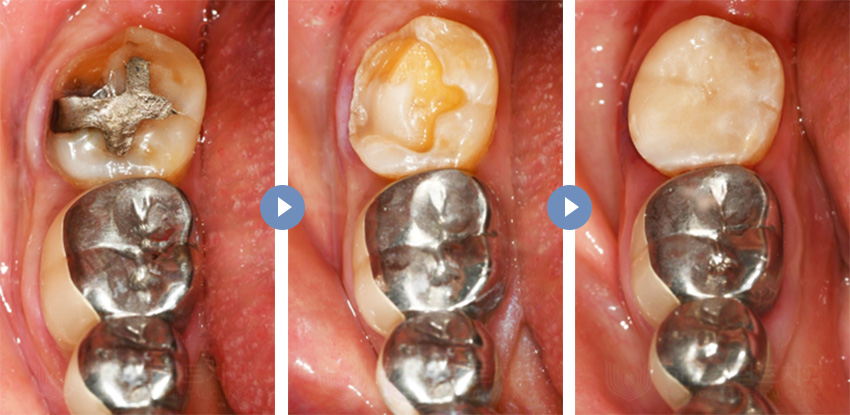

하루크라운은 기존의 복잡하고 시간이 많이 소요되는

크라운 치료 과정을 간소화하여

당일에 완료할 수 있도록 한 치료 방법입니다.

하루크라운 치료 전

하루크라운 치료 후

치료 시작과 동시에 치아를 삭제하고

컴퓨터 촬영을 통해 정확한 정보를 얻습니다.

하루플란트치과 원내 기공소에서

즉시 보철물을 제작하여

임시 치아 과정 없이 1~2시간 이내에

최종 보철물을 장착합니다.